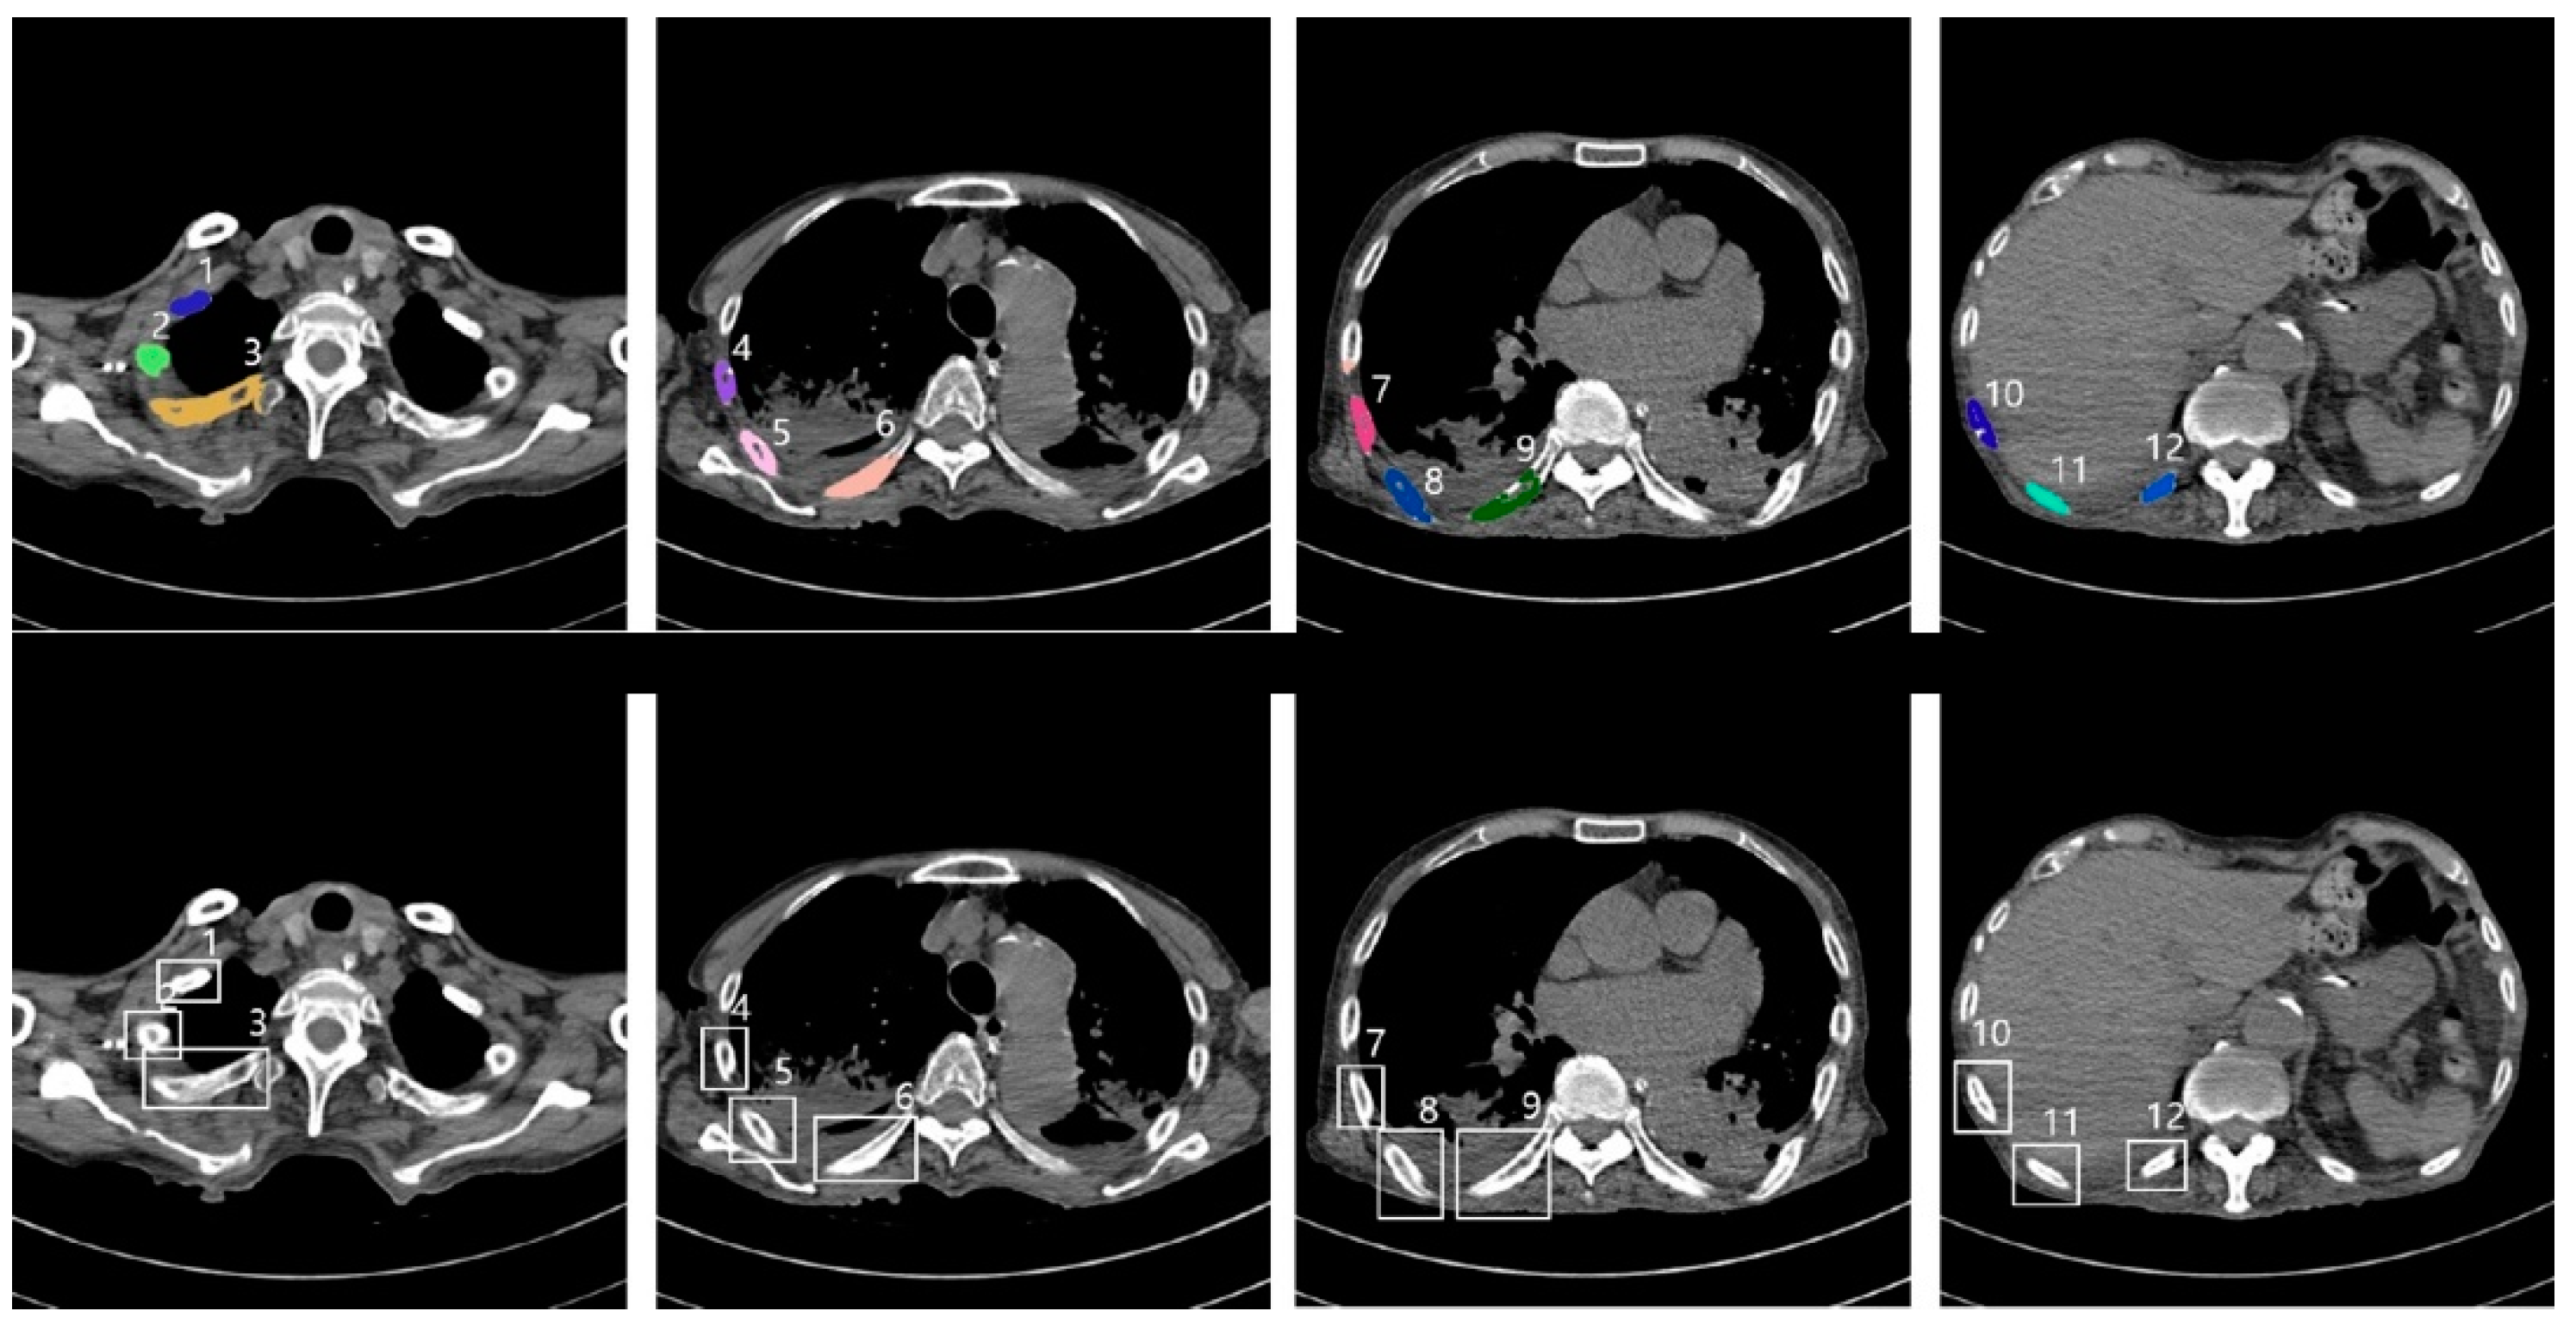

Figure 5 shows an example of successful automatic rib segmentation and sequence labeling (Figure 5). Intuitive results are displayed via colored labels and boxes in Figure 5. In addition, the result of sequence labeling is reconstructed on 3D rendering models with color annotations to verify the performance of the developed system (Figure 6).

Figure 5.

Results of sequence labeling; annotation for sequence labels with coloring (top) and boxes (bottom), including nearby numbers (1–12) labels indicating the order of the ribs from the top of the upper body (CNN, convolutional neural network).